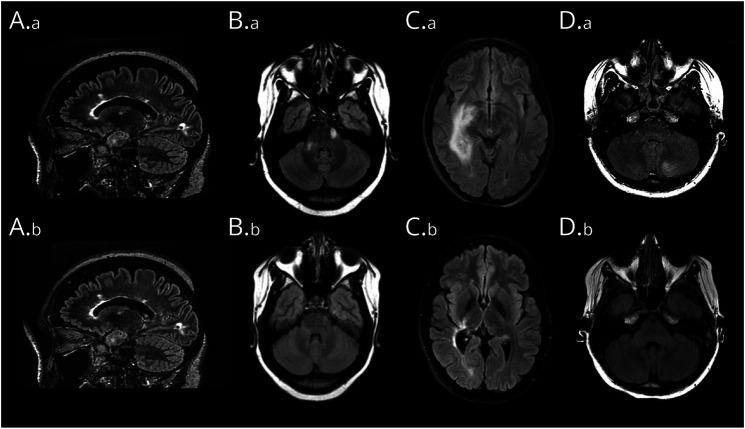

Results: Among the 255 patients included, 37 (14.5%) had limbic hyperintensities and 41 (16.1%) had extralimbic lesions that included multiple sclerosis (MS)-like lesions (14/41, 34.1%); extensive lesions (5/41, 12.2%); and poorly demarcated fluffy lesions, either multifocal (10/41, 24.4%) or involving the cerebral cortex or cerebellum (6/41 each, 14.6%). Extralimbic lesions coexisting with limbic lesions (19/41 patients, 46.3%) were mostly fluffy lesions (11/19, 57.9%). Ten patients had overlapping demyelinating syndromes: 4 with MS, 4 with myelin oligodendrocyte glycoprotein-associated disorder, and 2 with neuromyelitis optica spectrum disorder; all had MS-like (7/10 patients) or extensive (3/10 patients) lesions, and none had fluffy lesions. Extralimbic lesions were associated with symptoms nontypical for NMDARE (23/41, 56.1%, p < 0.001), especially cerebellar ataxia (17/41, 41.5%) and motor impairment (12/41, 29.3%). At 2 years, patients with MS-like or extensive lesions had a lower recovery rate (5/12, 41.7%, and 1/4, 25%, respectively) compared with the patients without extralimbic lesions (124/162, 76.5%; p = 0.014 and p = 0.047, respectively). In multivariable analysis, MS-like lesions, but not hippocampal nor fluffy lesions, were associated with absence of recovery at 2 years (adjusted OR 0.1, 95% CI 0.03-0.42, p = 0.002; extensive lesions [n = 4] not included in the analysis).

Discussion: Brain MRI lesions in NMDARE include limbic hyperintensities and 3 patterns of extralimbic lesions, which are associated with nontypical NMDARE symptoms. Moreover, MS-like and extensive lesions, but not fluffy nor hippocampal lesions, are associated with overlapping demyelinating syndromes and poor clinical outcomes at 2 years. These findings can have practical implications on the monitoring of patients with NMDARE.